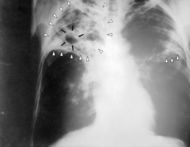

Tuberculosis-x-ray-1.jpg

Chest X-ray of a patient suffering from Tuberculosis

وتزداد هذه الأعراض حدة وشدة مع تطور المرض وقد يرافقها التقشع المدمى بكميات متفاوتة وكثيراً ما يكون هذا العرض هو الذي يدفع المريض لمراجعة الطبيب وعندها تكتشف الإصابة، وإن إثبات التشخيص لا يتم إلا بكشف عصيات كوخ في القشع ووجود ظلال شعاعية مرضية على صورة الصدر الشعاعية.

ويجب الاستعانة بالأشعة التي تعطي فكرة عن سعة الآفة ومكان توضعها وتطورها، وهل هي وحيدة الجانب أو مزدوجة.

تترواح موجودات صورة الصدر الشعاعية ما بين الطبيعية إلى شذوذات متنوعة مثل، اعتلال العقد اللمفية السرية، والعقد تحت الجؤجؤ subcarinal، والعقد المنصفية mediastinal أو انخماص أو ارتشاح قطعة segment أو فص رئوي أو انصباب جنب أو مرض دخني.